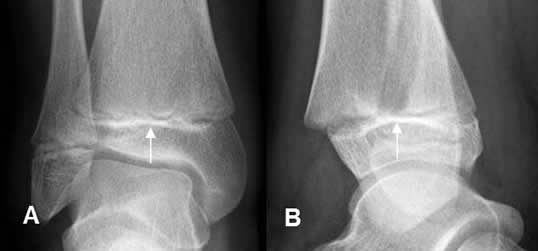

Fig 77. Salter tipo IV.

A: Rx AP y B: TAC reconstrucción sagital. Fracturas oblicuas con compromiso de las epífisis y metáfisis del tobillo y la rodilla.